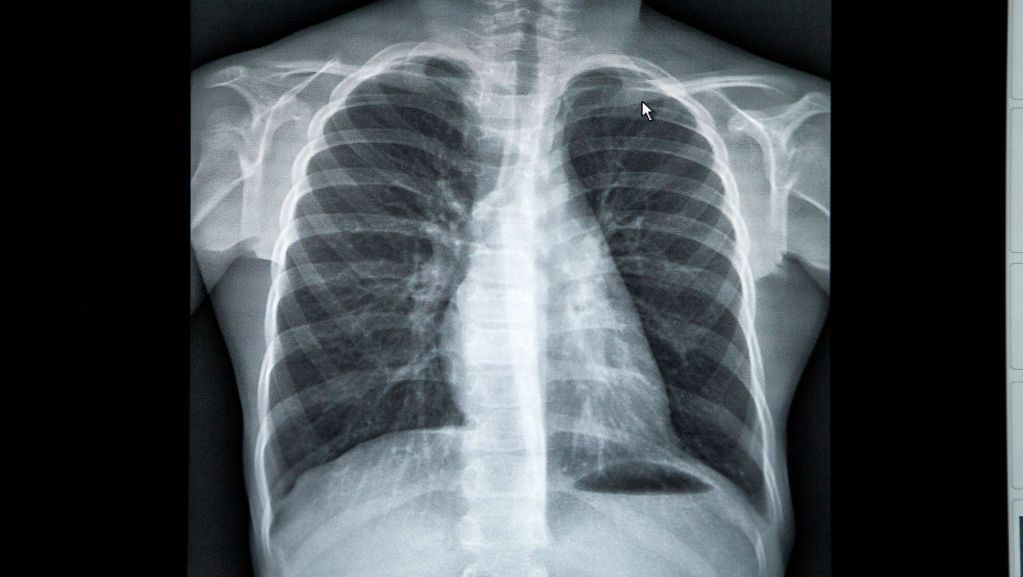

وقدّمت بانكهيد-كيندال 3 صور، الأولى لرئتي شخص سليم، والثانية تظهر رئتي شخص مدخّن في حين أن الثالثة تظهر رئتي شخص أصيب بـ”كورونا” وتعافى منه.

ووفقاً للصور، فإنّ رئتي الشخص السليم تبدو واضحة وغير ضبابية وليس عليها أي ندبات كما أنها غير مغطاة ببقع بيضاء، ما يدل على أنه لا يوجد احتقان، وهذا الشخص قادر على استنشاق كمية طبيعية من الأكجسين.

أما في ما خصّ رئتي الشخص المدخن، فقد غطاها البياض في أجزاء عديدة منها وقد بدت ضبابية بعض الشيء مع يشير إلى وجود بعض الاحتقان، في حين أن رئتي الشخص المتعافى من كورونا بدت بيضاء وضبابية بالكامل تقريباً وفيها ندبات شديدة، ما يشير إلى أن هذا الشخص يواجه صعوبات كبيرة جداً في التنفس وهناك احتقان شديد وكبير.

وتشير الضبابية في الرئتين وعدم ظهورها بشكل واضح إلى أنهما تعانيان من وجود سوائل أو بكتيريا تؤدي إلى سوء التنفس.